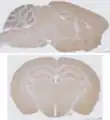

Sectional planes of the brain

Sagittal section (top) vs. coronal section (bottom) of a mouse brain